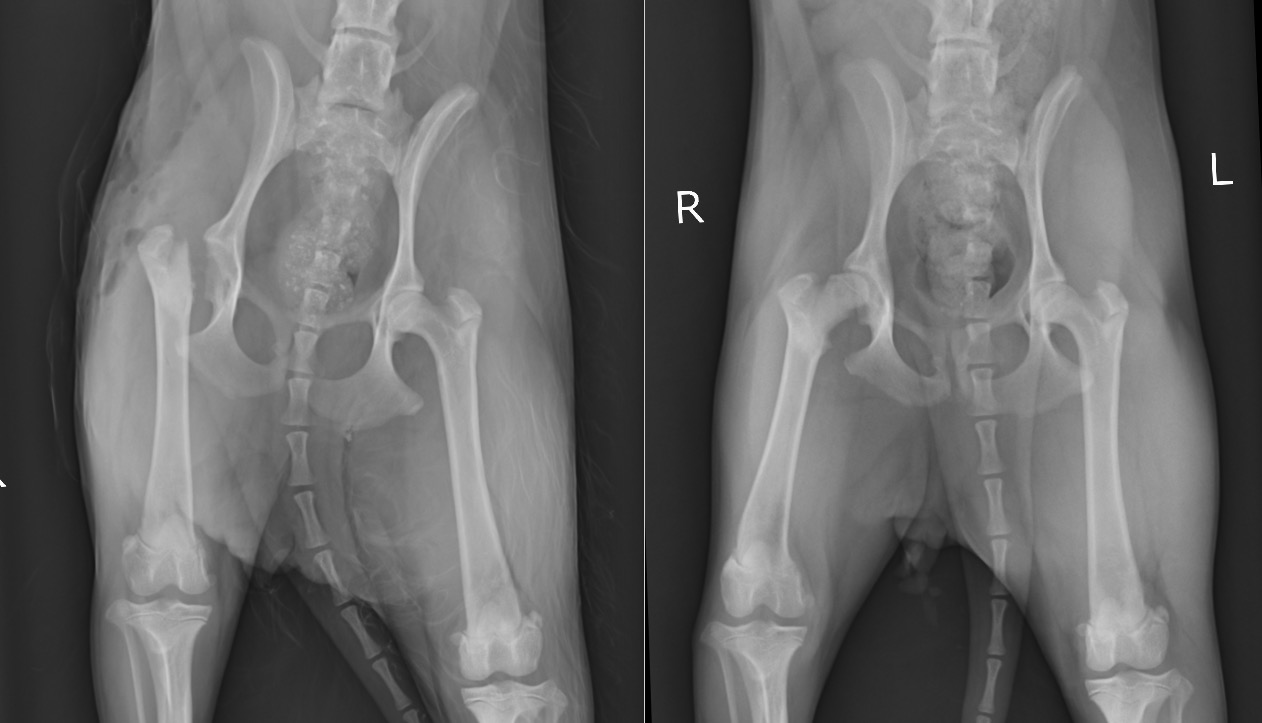

「1か月ほど前から右後ろ足を気にしてお散歩中に足を挙げてしまうことがある」という症状で来院した小型MIXのわんちゃんで年齢は1歳未満でした。

整形外科学的検査において、右後肢の負重性跛行、右殿筋~大腿にかけての筋萎縮、右股関節の伸展痛が認められたためX線検査を実施いたしました。

また右の大腿部の筋肉量が左に比べてだいぶ細いこともよく分かります。(緑線)

痛みのある右の後ろ足をかばいなるべく体重をかけず使わないように生活していた結果の筋萎縮だと考えられます。

LCPDは何らかの原因で大腿骨頭への血液供給が阻害され(虚血)、組織障害を引き起こす病態とされていますが、原因は分かっていません。多くは1歳未満の若齢のトイプードルやポメラニアンなどの小型犬で認められます。